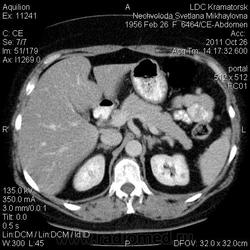

Здравствуйте! Вот уже месяц не могут поставить диагноз. Первичный очаг найти не удалось. Множественная миелома (несекретирующая?, т.к. по крови стерн. пункция не дает результата)?

Была взята биопсия с пораженного позвонка, но в материале оказалось мало клеток кости, наличие фиброзных клеток. Материал трепанбиопсии правой подвздошной так же содержал мало клеток, т.к. удалось углубиться всего лишь на 7мм (дальше сломалась игла, по словам врача скорее всего об фиброзное образ.). Можно ли по результатам КТ предложить повторный, более прицельный поиск? Что еще говорит КТ?

По имеющимся файлам-дайком я не нашла признаков опухоли. Имеется множественное остеолитическое поражение позвоночника, ребер, грудины, частично - таза. Лимфоузлы не увеличены. Тоже поставила бы на первое место миеломную болезнь. Диагностирование её не всегда простое дело. Поражена грудина и, наверное, нужно посоветоваться с онкологом (гематологом) стоит ли сделать стернальную пункцию.Советую написать в личку tatyana.

Думаю тоже в первую очередь здесь миеломная болезнь, процентов на 80%. Но результаты лабораторных анализов действительно неоднозначные.

Повторюсь: по имеющимся данным наиболее вероятной считаю миеломную болезнь